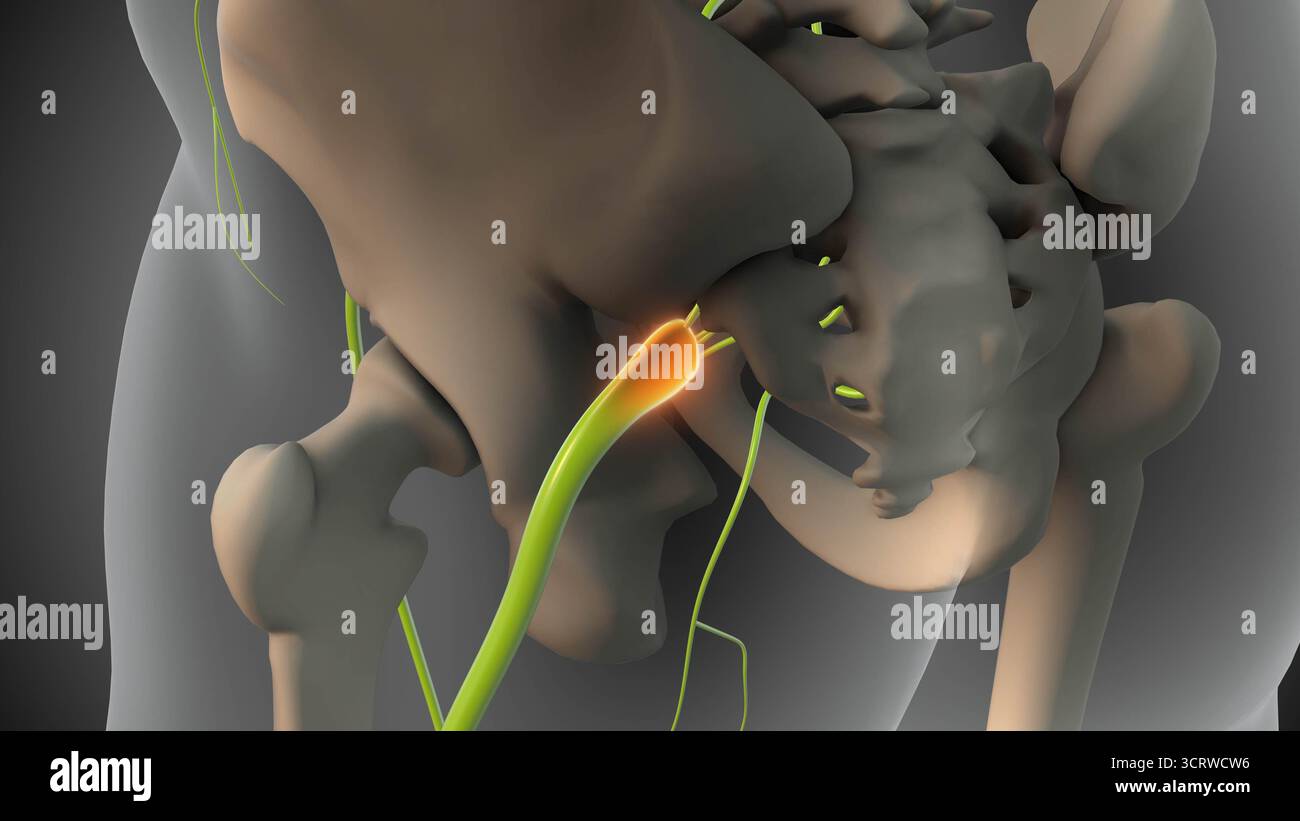

Bassin avec tumeur du nerf sciatique Banque D'Imageshttps://www.alamyimages.fr/image-license-details/?v=1https://www.alamyimages.fr/bassin-avec-tumeur-du-nerf-sciatique-image703110722.html

Bassin avec tumeur du nerf sciatique Banque D'Imageshttps://www.alamyimages.fr/image-license-details/?v=1https://www.alamyimages.fr/bassin-avec-tumeur-du-nerf-sciatique-image703110722.htmlRF3CRWCW6–Bassin avec tumeur du nerf sciatique